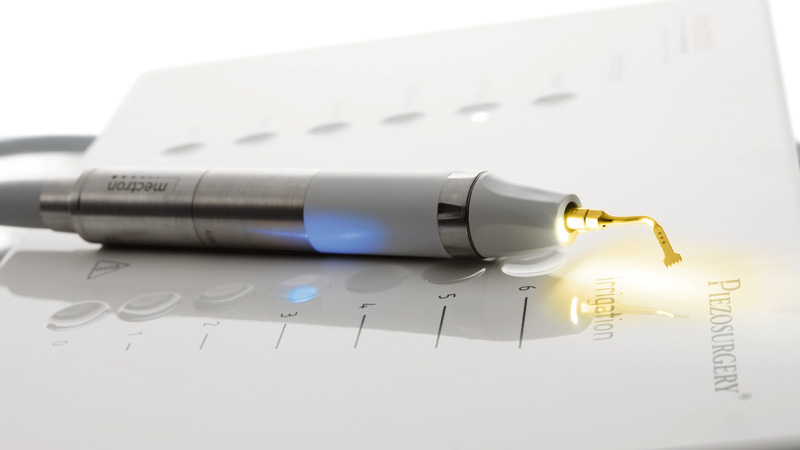

Inoltre, grazie all’impiego della innovativa tecnologia Piezosurgery®, siamo in grado di programmare l’inserimento degli impianti, anche in zone in cui ci sia poco osso, in modo minimamente invasivo grazie al taglio micrometrico, con massima precisione e senza ledere vasi e nervi.

Maggiore sicurezza per voi e maggiore predicibilità per noi.